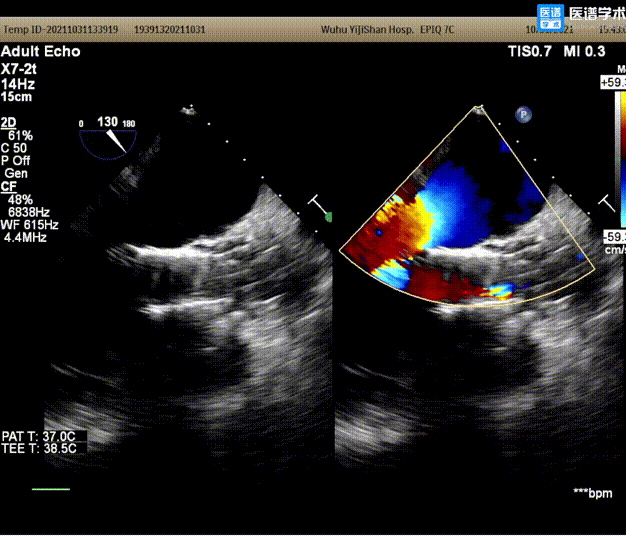

6. 回收后进行重新定位释放,释放完毕后超声评估示平均跨瓣压差15mmHg,超声、造影评估示中量瓣周漏、少量瓣中漏,瓣膜整体下滑明显,遂行瓣中瓣策略;

7. 选择沛嘉TaurusElite AV26号瓣膜执行瓣中瓣策略,第二个瓣膜释放后造影示瓣周漏改善不明显,遂选用TaurusAtlas 22mm 球囊行后扩张;

8. 扩张后跨瓣压差降至8mmHg,造影示轻微瓣周漏,患者血流动力学指标改善明显,手术圆满成功。

• 由于本例患者的低钙化特性,第一个瓣膜最终释放后,仍不免位移。但基于良好的术前策略制定,汤圣兴教授团队迅速完成瓣中瓣释放,并基于血流动力学参数进行了后扩张操作,最终为患者带来了明显的临床获益。